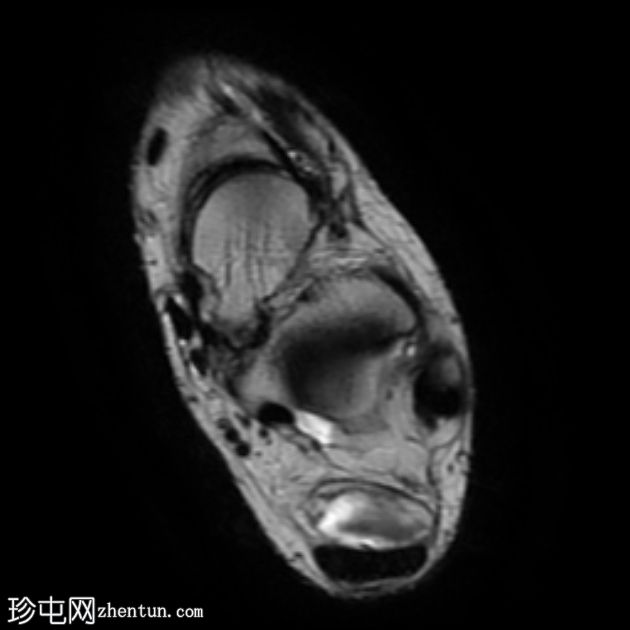

轴向

T1

T2

STIR

跟腱插入

,伴有跟腱明显增厚,可诱发异常信号、跟腱后滑囊炎、跟骨后突及骨髓水肿信号。

Haglund综合征的检查结果令人印象深刻。

Haglund综合征是指以下三联征(Haglund三联征):

跟腱插入性病

跟腱后滑囊炎

Haglund畸形(即跟骨后上外生骨疣)